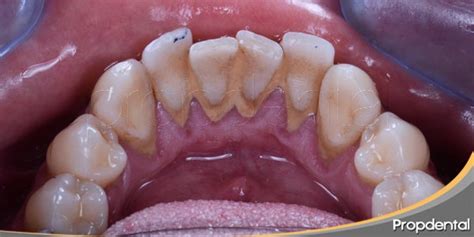

El sarro cuando se forma es de color blanquecino pero a medida que pasa el tiempo se va poniendo amarillo y luego marrón. El color del sarro depende de la edad y de dónde aparece en la boca. El sarro sobre la línea de las encías, también denominado cálculo supragingival, es amarillo o tostado. El cálculo subgingival es el sarro que aparece debajo de la línea de las encías, el cual puede ser marrón, negro o verde.

El cálculo dental es fácil de identificar ya que se encuentra en la parte superior al límite de las encías. El indicador de sarro más común es observar un color marrón o amarillento en los dientes o encías. Uno de los elementos esenciales que se perciben es que los dientes estén manchados de un color amarillento o marrón.

- Cálculo supragingival: Cuando los depósitos se ubican por encima de las encías hablamos de cálculo supragingival.

- Cálculo subgingival: Son aquellos depósitos que se ubican debajo de la zona gingival. Estos cálculos son de color marrón oscuro o verdoso. Es habitual que se encuentre en las zonas linguales y proximales. Se ubica por debajo de la línea de la encía, focalizándose a su vez en la raíz del diente, siendo poco visible lo que hace que sea más dañino.

Existen dos tipos de sarro, el supragingival que es el que se puede observar a simple vista y el subgingival que no es visible y es el más perjudicial para las encías y los tejidos de soporte del diente (hueso).